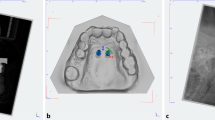

Postoperative CBCT scans (Galileos, Sirona, Bensheim, Germany; 98 kV, 25 mAs, effective radiation time 5 s, FOV: diameter 215 mm, voxel size 160 μm) were performed after the heads were aligned with optical localizers to the midsagittal plane and Frankfurt horizontal plane to ensure symmetry. Then, the scans were transformed into the Digital Imaging and Communications in Medicine (DICOM) format and imported with the virtual cast models into the coDiagnostiXTM software (version 9, Dental Wings GmbH, Freiburg, Germany). The outcome assessment was blinded. In all cases, the maximum possible superposition was adjusted using the automatic software function. For this purpose, the cast model was matched to at least three clearly visible matching references distributed over the arch (Fig. 2). The vestibular tooth surfaces including occlusal surfaces of the first molars as well as the distoincisal angle of the left/right central incisors were defined as references. Three-dimensional measurements (coronal, sagittal, and axial planes) included the distances between the matched files of the implant axis, implant tip and centre of the implant shoulder (Fig. 3a). Between the planned and postoperative vertical implant positions, the distances between the anterior and posterior implant shoulders and the contact of the gingiva at the implant in the sagittal planes were evaluated (Fig. 3b).

Three-dimensional measurements between the superpositioned files of the deviations of the implant axis (a), implant tip (b) and implant shoulder (c). Evaluation of the distance between the vertical implant position of the anterior (d) and posterior implant shoulder (e) to the contact of the gingiva at the implant. Measurements of the anterior and posterior vertical implant position were performed twice: during preoperative planning (d) and during postoperative CBCT scans (e)